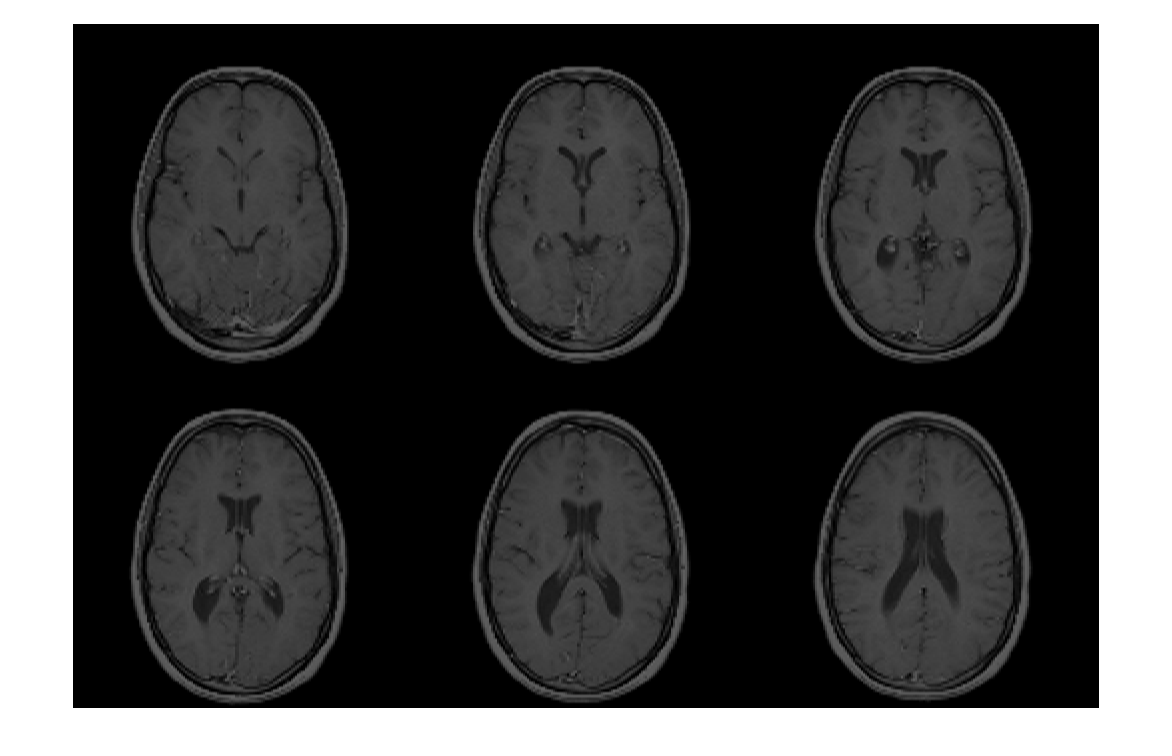

Считайте данные изображения из файла Analyze 7.5.

X = analyze75read('brainMRI');

Просмотрите данные. Во-первых, потому что формат Analyze 7.5 использует радиологическую ориентацию (LAS), инвертируйте данные для отображения правильного образа в MATLAB.

X = flip(X);

Затем измените данные, чтобы создать массив, который может быть отображен с помощью montage. Выберите кадры 12 - 17.

Y = reshape(X(:,:,12:17),[size(X,1) size(X,2) 1 6]);

montage(Y);